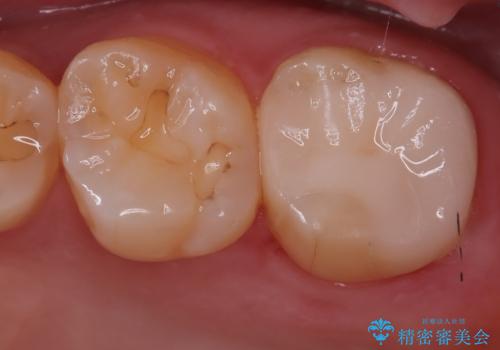

[ オールセラミッククラウン ] すき間の目立つ前歯をきれいにしたい!

担当医 大元洋佑